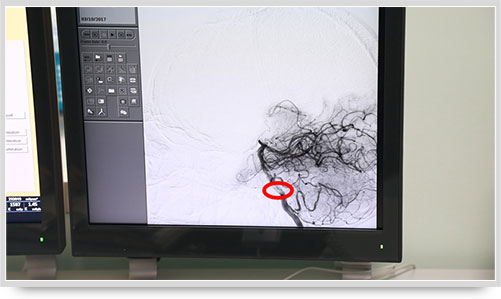

病變血管一目了然

45歲的朱姓患者因“多發(fā)性腔性腦梗塞”頭暈不明,接受了全腦血管造影術(shù),術(shù)中顯示他的顱內(nèi)椎動脈血管痙攣(紅圈內(nèi)為病變部位)。據(jù)李主任介紹,以前像腦梗塞等腦血管疾病只能被定位到腦的功能區(qū)域,無法確定責(zé)任血管,而實施全腦血管造影術(shù)就能精準(zhǔn)地找出病變血管,好比揪出了造成腦梗塞的“禍?zhǔn)?rdquo;,大大提高了腦血管疾病的診治水平。

之前,另一位61歲的李姓腦出血患者,康復(fù)治療半個月后復(fù)查,也接受了全腦血管造影術(shù),術(shù)中顯示大腦前動脈A1段動脈瘤(不同維度顯影,紅圈內(nèi)為動脈瘤瘤體)。像這樣的病人,必須進(jìn)一步進(jìn)行手術(shù)治療,及早清除動脈瘤,避免因瘤體破裂造成再次出血危及生命。